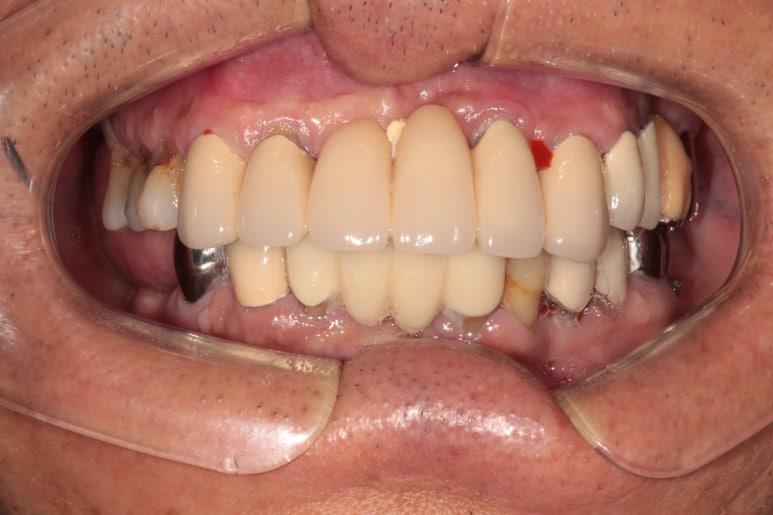

정면 사진입니다! 사실 앞니는 가지고 계신 그대로 사용하고 있어 큰 변화가 없어 보입니다만..

상당히 가지런히 구성지게 어금니를 만들어드린 것을 보실 수 있을거에요!

우측 어금니를 보시면, 너무나 많은 치석으로 인해 만성치주염에 시달렸던 치아들은 사라지고, 이제 깔끔하게 임플란트로 대체된 것을 보실 수 있습니다.

임플란트는 보통 1 piece로 제작되기 때문에, 기존에 흔들리고 잇몸이 올라가버린 어금니보다 오히려 음식도 덜 끼고.. 사용하기 상당히 좋은 환경이 조성되었지요.